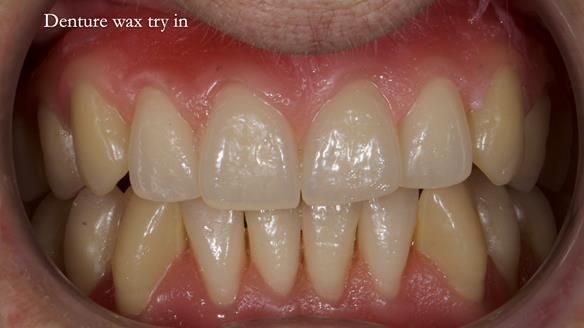

This is Newsletter 83, and it’s all about Sheila’s journey — from years of denture failure, flat ridges and a small mouth opening, to a stable, comfortable set of complete dentures that changed her confidence and daily life. We also copied Kirsty MacColl’s smile, which made the process even more enjoyable for her.

Welcome to Newsletter 83. This month I am sharing Sheila’s case — a very challenging but rewarding complete denture case. Sheila had flat ridges, a small mouth opening, a large tongue and had never been able to wear complete dentures of any kind. Everything was loose and sore. She felt embarrassed and looked older without dentures. She wanted a stable, comfortable result, and she wanted to avoid implants because she has taken bisphosphonates for more than five years.

In this newsletter I will take you through Sheila’s full protocol step by step — including impressions, French Impression Technique, Dr Abe shaping, copying Kirsty MacColl’s smile, the try-in, the final fit, and the copy dentures we made afterwards.